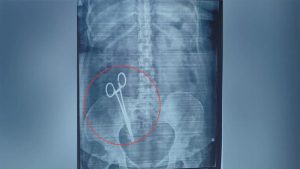

लखनऊ। यूपी की राजधानी लखनऊ से एक हैरान कर देने वाला मामला सामने आया है। यहां एक महिला के पेट में डॉक्टरों ने 17 साल पहले कैंची छोड़ दी थी। मामले का खुलासा तब हुआ जब महिला का एक्स-रे कराया गया। वहीं एक्स-रे की रिपोर्ट मिलने के बाद महिला के पेट में कैंची होने की बात सामने आई, जिसके बाद परिजनों के होश उड़ गए। बताया जा रहा है कि महिला का 17 साल पहले ऑपरेशन हुआ था, जिसके बाद से ही कैंची पेट में थी। वहीं घटना सामने आने के बाद महिला के पति ने गाजीपुर थाने में लापरवाही बरतने वाली डॉक्टर के खिलाफ शिकायत दर्ज कराई है।

दरअसल, लखनऊ में एक महिला का एक्स-रे कराने के बाद उसके पेट में कैंची होने की बात सामने आई। इस घटना के बाद महिला के पति ने गाजीपुर थाने में शिकायत दर्ज कराई है। वहीं KGMU में ऑपरेशन के बाद महिला के पेट से कैंची को निकाला गया है। महिला के पति अरविंद पांडे ने शिकायत में बताया है कि उन्होंने 26 फरवरी 2008 को अपनी पत्नी को इंदिरानगर के ‘शी मेडिकल केयर’ में भर्ती कराया था। यहां डॉक्टर पुष्पा जायसवाल के द्वारा ऑपरेशन किया गया, जिससे उन्हें बच्चा पैदा हुआ। ऑपरेशन के कुछ समय बाद तक सब ठीक रहा, लेकिन कुछ दिनों के बाद महिला को विभिन्न प्रकार की समस्या होने लगी।

पीड़ित ने शिकायत में आगे कहा है कि वह काफी लंबे समय से अपनी पत्नी का इलाज करा रहा था। इस बीच 23 मार्च 2025 को जब उसने अपनी पत्नी का एक्स-रे कराया तो पेट में कैंची होने की बात पता चली। इसके बाद उन्होंने अपनी पत्नी को केजीएमयू में दिखाया। यहां 25 मार्च 2025 को मेडिकल परीक्षण के बाद उनकी पत्नी को भर्ती कर लिया गया और 26 मार्च 2025 को ऑपरेशन के पश्चात पेट से कैंची निकाली गई। पीड़ित ने लापरवाह डॉक्टर पुष्पा जायसवाल के खिलाफ कार्रवाई की मांग की है।